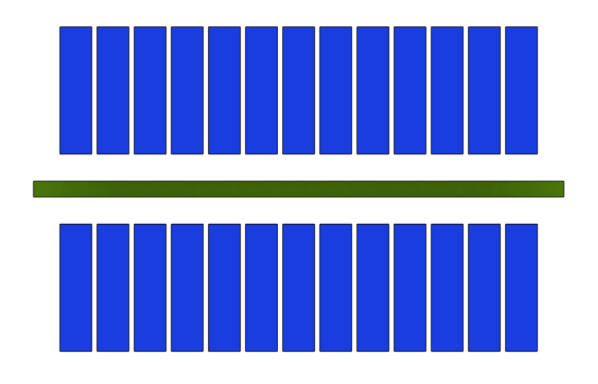

The J-PEM is a prototype intended to evaluate PET technology in the diagnosis of malign neoplasm in the breast and of ganglion loco-regional invasion. It is based on plastic scintillators and utilizes the same technology as the Jagiellonian Positron Emmision Tomograph, J-PET [31]. It is optimized for the detection of photons from electron-positron annihilation [32, 33]. Such photons, having an energy of 511 keV, interact with electrons in plastic scintillators predominantly via the Compton effect. J-PEM uses a dedicated instrument for breast cancer detection that is equipped with two parallel photon detectors in a configuration similar to mammography compressors. The detector system consists of two modules of plastic scintillators, with each module built from two layers of plastic scintillator and the wavelength shifters [34, 35] placed orthogonally between them, as shown in Fig. 6. Each scintillator bar is attached at both ends with Silicon Photomultipliers for the signal readout [32]. The combined use of plastic scintillators, which have superior timing properties, with the WLS strips can provide an affordable and precise scanner with significant improvement in spatial resolution and efficiency for the detection of breast cancer. Plastic scintillators are characterized by short light decay time which is in the order of 1.5 ns [32]. This enables one to achieve high time resolution. In the J-PET, solution for the position of the interaction point of photons is based on the measurement of the time of the signals arrival to the ends of the long scintillator strips. So far a resolution of about 10 mm was achieved [35]. In order to achieve high resolution, we propose to register scintillation light escaping the scintillator bar through a side wall using an array of WLS. It has been already proven that one can reach to position resolution of 5 mm for the coordinate along the scintillator bar.